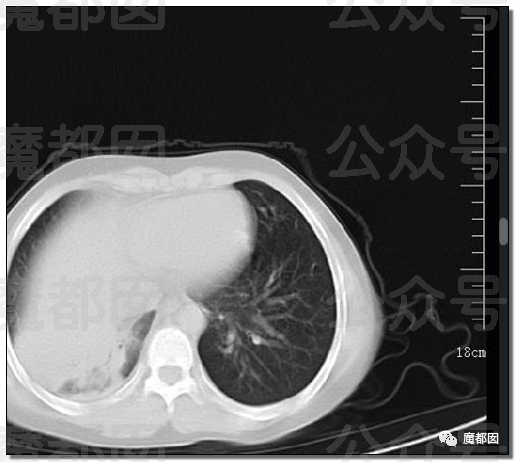

我们都晓得,正常情况下肺部是由肺泡组成的,肺泡里边是充满了空气的,进行CT或者是X线检查的时候,射线穿过肺泡的时候,影像的表现应该是黑色的区域,但是当肺泡里边出现炎症和感染,有渗出液和炎性细胞的时候,肺泡就被这些渗出液或者炎性细胞填充,这样射线就穿不透,在影像学上的表现就出现了白色的区域,这个白色区域反映出来的是渗出物的影像学的表现。

随着这些渗出液的吸收、炎症的消退,白肺的表现也会逐渐消退,也就是说肺部的影像学表现就会回到正常的黑色的区域。并不是只要肺部出现了炎症就都叫白肺,比较严重的肺炎的表现才会出现白肺,一般来讲肺部的炎症比较重,渗出比较多的时候,就是白色的影像区域面积达到了70%到80%的时候,才在临床上把它称为白肺。

白肺会有什么后果?本质上和淹死一个道理。肺被病毒(也可以是细菌等其他微生物)导致的果冻状的分泌物给占满了,肺的换气功能完全丧失。再浓的氧也进不去血里面。而吸痰,做过气管镜的都知道,靠气管镜到达不了那个终末端的地方。另外,没有特效药。

肺白之后,就容易纤维化,而纤维化后的肺在目前医学上无任何药物可逆转和治疗,除非进行肺移植,也就是换肺。重症的白肺患者,死亡率在40%以上,还是有一部分人是可以治愈的。但是要想让肺恢复到本来干干净净的状态,是比较难的,绝大部分患者会留下肺部纤维化的后遗症。